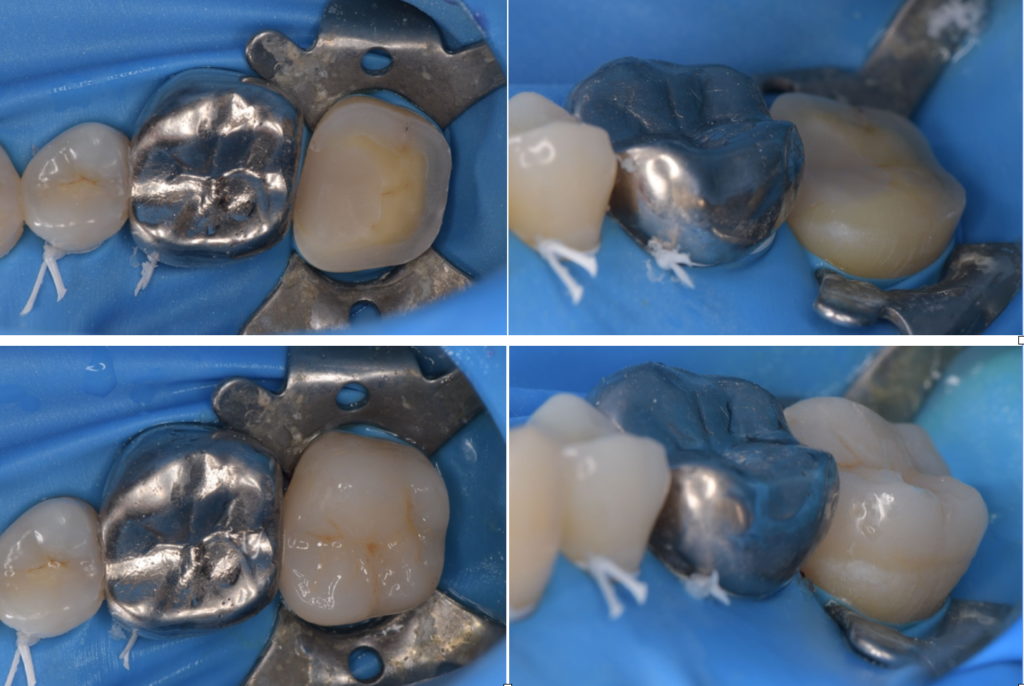

接着ラバーダム

根管治療、虫歯治療、接着修復時において、可能な限り無菌的な環境で行うことが最も重要です。